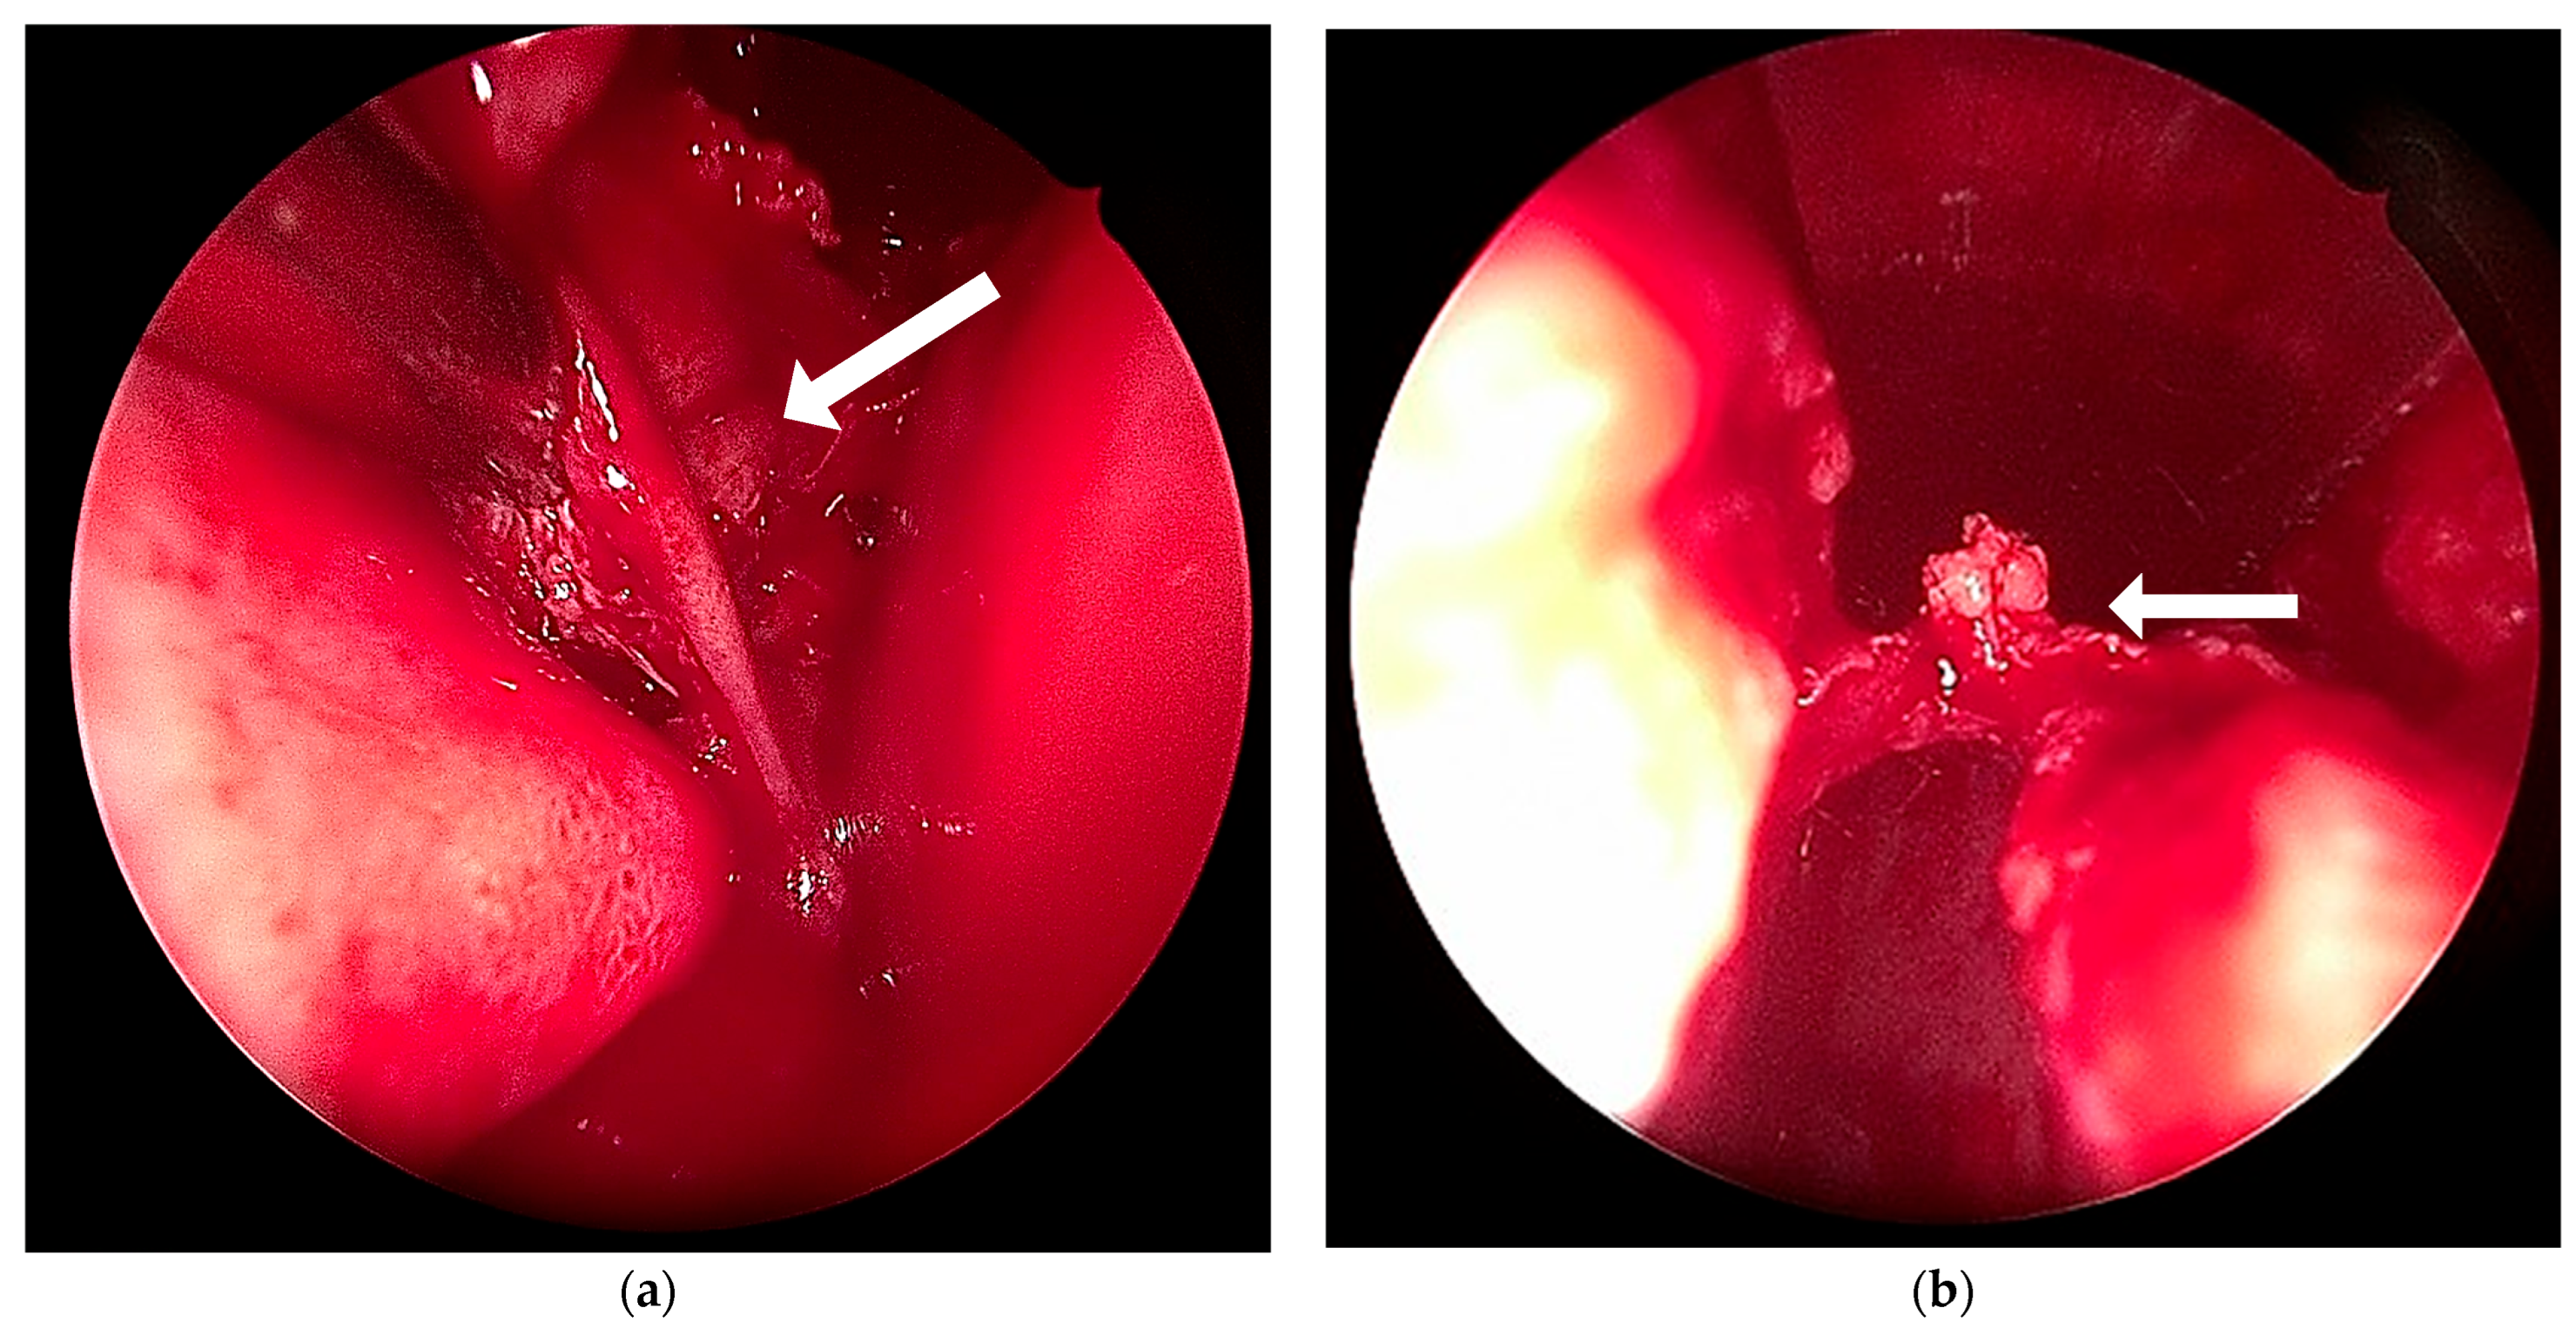

2.3. Treatment and Outcome